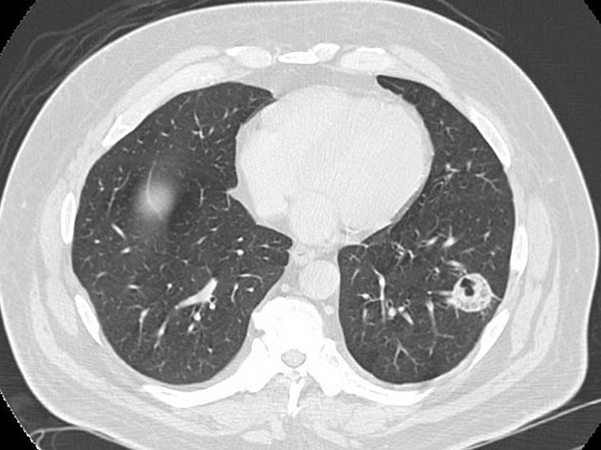

Clinical History: A man in his 50s being treated for bilateral angiomyolipomas with everolimus underwent a routine follow-up abdominal CT, which revealed a lung lesion. A dedicated chest CT confirmed the presence of a 2.5-cm cavitary nodule in the lower lobe of the left lung (Figure 1). The lesion was hypermetabolic (SUV 2.5). He was a current smoker (>40 pack years). There was no other significant history.

Imaging findings of pulmonary mucormycosis include the reverse halo sign (ground-glass opacity surrounded by consolidation), the halo sign, consolidation alone, pleural effusion, nodules, masses and cavitation. None of these features are specific for mucormycosis, and many of them also occur in pulmonary aspergillosis.